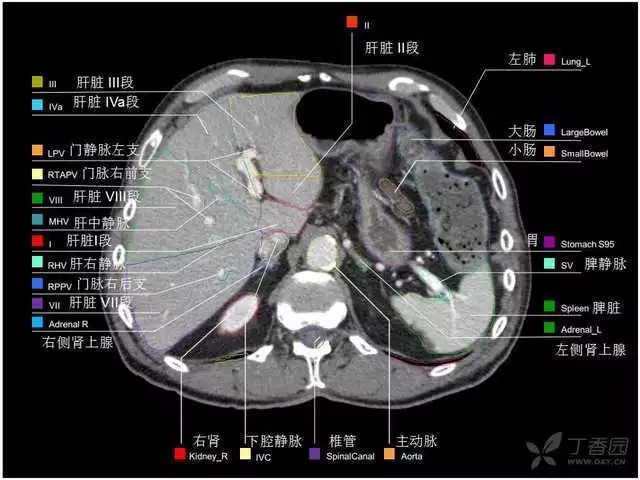

腹部肝脏高清CT断层的图谱

全腹部高清CT图谱,淋巴结彩色图谱,血管解剖图谱大汇总!

超声肝脏分叶及分段

肝脏分段和基本解剖学标志